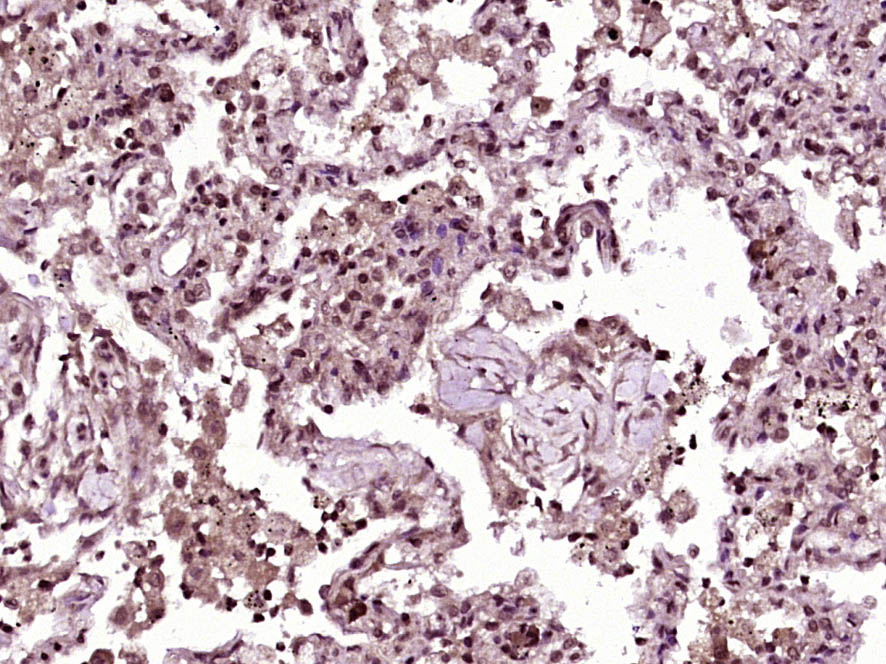

Paraformaldehyde-fixed, paraffin embedded (Human lung carcinoma); Antigen retrieval by boiling in sodium citrate buffer (pH6.0) for 15min; Block endogenous peroxidase by 3% hydrogen peroxide for 20 minutes; Blocking buffer (normal goat serum) at 37°C for 30min; Antibody incubation with (INSM1) Polyclonal Antibody, Unconjugated (bs-16675R) at 1:400 overnight at 4°C, followed by operating according to SP Kit(Rabbit) (sp-0023) instructionsand DAB staining.

Paraformaldehyde-fixed, paraffin embedded (Human pituitary tumor); Antigen retrieval by boiling in sodium citrate buffer (pH6.0) for 15min; Block endogenous peroxidase by 3% hydrogen peroxide for 20 minutes; Blocking buffer (normal goat serum) at 37°C for 30min; Antibody incubation with (INSM1) Polyclonal Antibody, Unconjugated (bs-16675R) at 1:400 overnight at 4°C, followed by operating according to SP Kit(Rabbit) (sp-0023) instructionsand DAB staining.